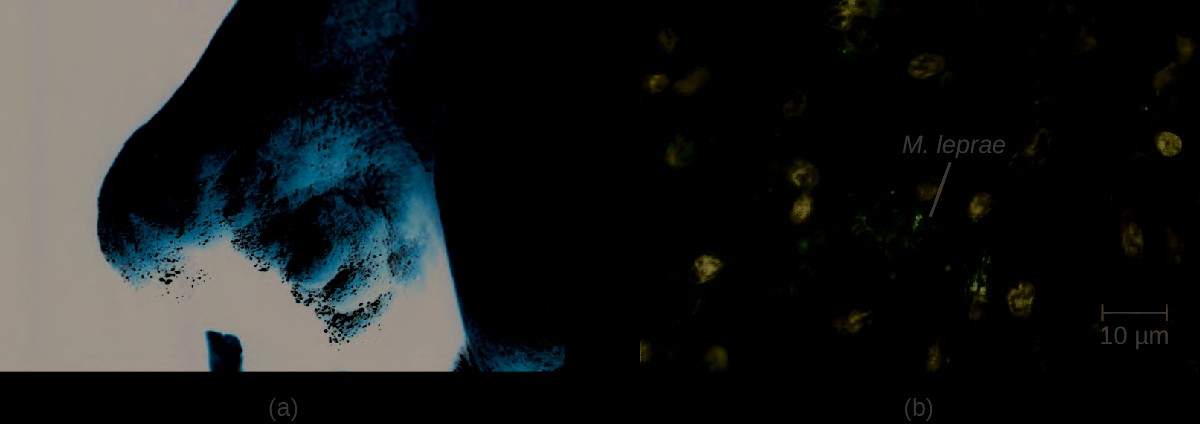

Hansen’s Disease (Leprosy)

Hansen’s disease (also known as leprosy) is caused by a long, thin, filamentous rod-shaped bacterium Mycobacterium leprae, an obligate intracellular pathogen. M. leprae is classified as gram-positive bacteria, but it is best visualized microscopically with an acid-fast stain and is generally referred to as an acid-fast bacterium. Hansen’s disease affects the PNS, leading to permanent damage and loss of appendages or other body parts.

Hansen’s disease is communicable but not highly contagious; approximately 95% of the human population cannot be easily infected because they have a natural immunity to M. leprae. Person-to-person transmission occurs by inhalation into nasal mucosa or prolonged and repeated contact with infected skin. Armadillos, one of only five mammals susceptible to Hansen’s disease, have also been implicated in transmission of some cases.[16]

In the human body, M. leprae grows best at the cooler temperatures found in peripheral tissues like the nose, toes, fingers, and ears. Some of the virulence factors that contribute to M. leprae’s pathogenicity are located on the capsule and cell wall of the bacterium. These virulence factors enable it to bind to and invade Schwann cells, resulting in progressive demyelination that gradually destroys neurons of the PNS. The loss of neuronal function leads to hypoesthesia (numbness) in infected lesions. M. leprae is readily phagocytized by macrophages but is able to survive within macrophages in part by neutralizing reactive oxygen species produced in the oxidative burst of the phagolysosome. Like L. monocytogenes, M. leprae also can move directly between macrophages to avoid clearance by immune factors.

The extent of the disease is related to the immune response of the patient. Initial symptoms may not appear for as long as 2 to 5 years after infection. These often begin with small, blanched, numb areas of the skin. In most individuals, these will resolve spontaneously, but some cases may progress to a more serious form of the disease. Tuberculoid (paucibacillary) Hansen’s disease is marked by the presence of relatively few (three or less) flat, blanched skin lesions with small nodules at the edges and few bacteria present in the lesion. Although these lesions can persist for years or decades, the bacteria are held in check by an effective immune response including cell-mediated cytotoxicity. Individuals who are unable to contain the infection may later develop lepromatous (multibacillary) Hansen’s disease. This is a progressive form of the disease characterized by nodules filled with acid-fast bacilli and macrophages. Impaired function of infected Schwann cells leads to peripheral nerve damage, resulting in sensory loss that leads to ulcers, deformities, and fractures. Damage to the ulnar nerve (in the wrist) by M. leprae is one of the most common causes of crippling of the hand. In some cases, chronic tissue damage can ultimately lead to loss of fingers or toes. When mucosal tissues are also involved, disfiguring lesions of the nose and face can also occur ( Figure 26.11).

Hansen’s disease is diagnosed on the basis of clinical signs and symptoms of the disease, and confirmed by the presence of acid-fast bacilli on skin smears or in skin biopsy specimens (Figure 26.11). M. leprae does not grow in vitro on any known laboratory media, but it can be identified by culturing in vivo in the footpads of laboratory mice or armadillos. Where needed, PCR and genotyping of M. leprae DNA in infected human tissue may be performed for diagnosis and epidemiology.

Figure 26.11 (a) The nose of a patient with Hansen’s disease. Note the lepromatous/multibacillary lesions around the nostril. (b) Hansen’s disease is caused by Mycobacterium leprae, a gram-positive bacillus. (credit a, b: modifications of work by the Centers for Disease Control and Prevention)